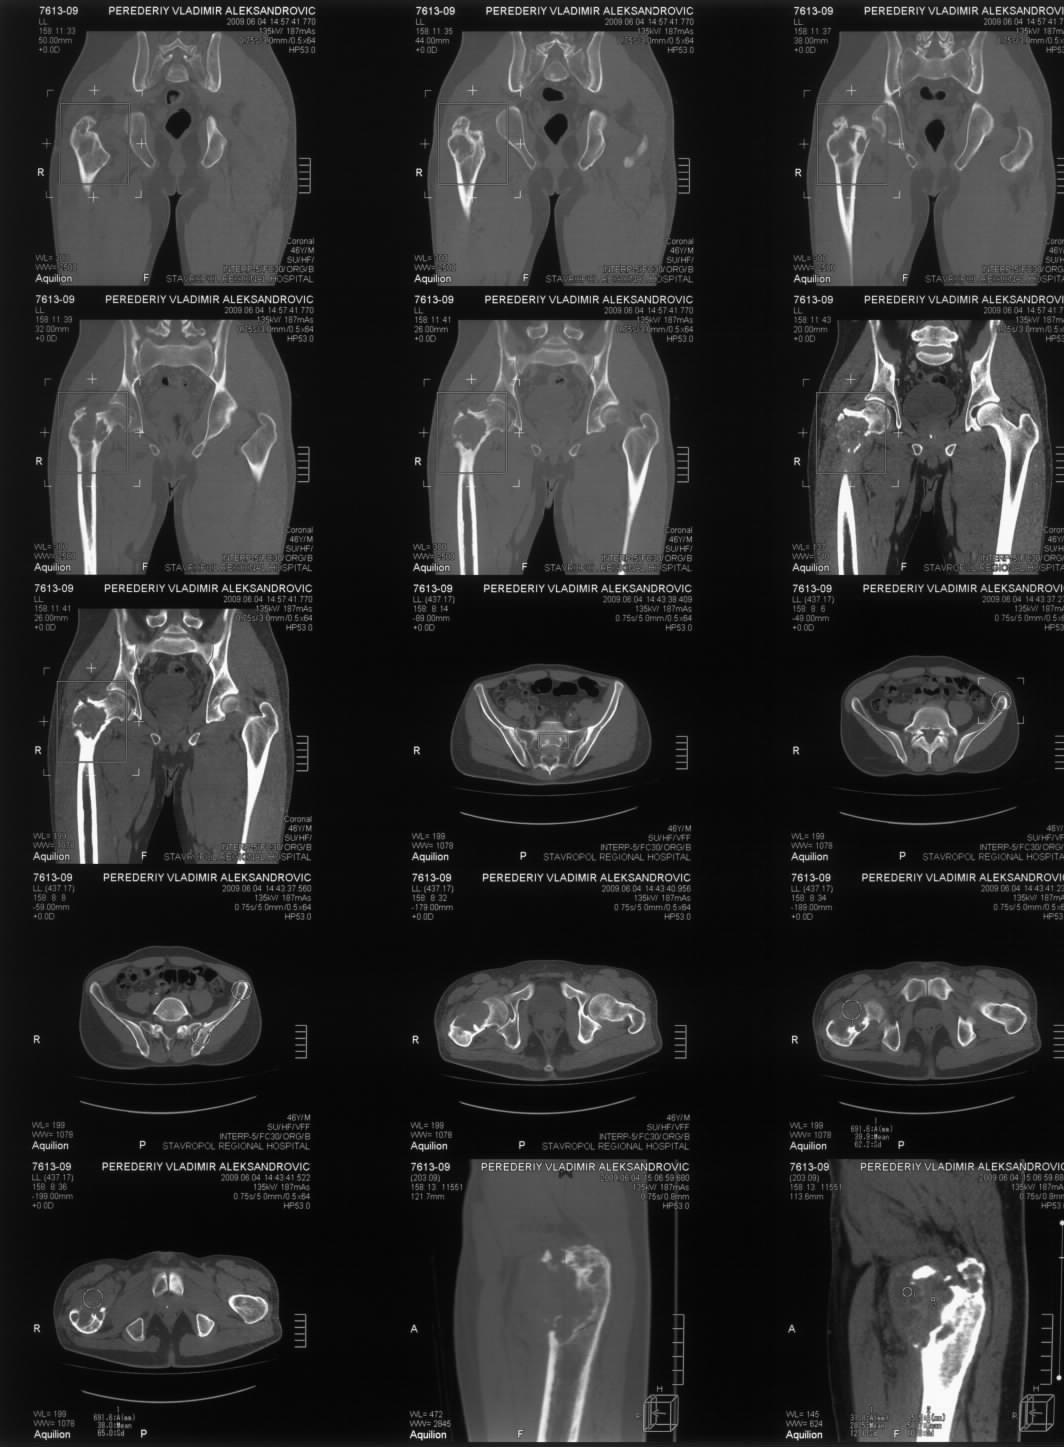

Диагноз: Ангиосаркома проксимального отдела правой бедренной кости. Патологический перелом шейки бедренной кости. Множественные метастазы в легкие, позвоночник, ребра, кости таза.

Считает себя больным с 2005 года, когда впервые появились боли в правом тазобедренном суставе с иррадиацией в поясничную область. Лечился по месту жительства по поводу поясничного остеохондроза, люмбоишиалгии. Отмечает постепенное усиление болей в области правого тазобедренного сустава. С августа 2007 года появилась хромота. В 2008 году была выполнена рентгенография тазобедренного сустава, выявлен патологический очаг в проксимальном отделе бедренной кости. Консультирован онкологом. Обследовался стационарно в травматолого-ортопедическом отделении №1 ГУЗ «СККЦ СВМП». Была выполнена операционная биопсия. Заключение: «наиболее вероятна картина гемангиоэндотелиомы с явлениями пролиферации и атипии». Для дальнейшего лечения был направлен в РОНЦ им. Н.Н.Блохина РАМН. Повторно была выполнена операционная биопсия с иммуногистохимическим исследованием материала. Заключение: «морфологическая картина более всего соответствует ангиосаркоме». Получил курс лучевой терапии. Планировалась повторная госпитализация для органосохраняющего оперативного лечения. Однако до настоящего времени госпитализация не состоялась.

31.05.09 упал дома с высоты собственного роста. Появились сильные боли в правом тазобедренном суставе. Самостоятельно обратился в ГУЗ «СККЦ СВМП». При клиническом обследовании и рентгенографии был диагностирован патологический перелом шейки бедренной кости.Объективно:

Имя     : MRT.JPG

Тип     : image/jpeg

Размер  : 135763 байтов

Описание: отсутствует

Url     : http://weborto.net:8080/pipermail/ortho/attachments/20090619/8925512e/attachment-0002.jpeg